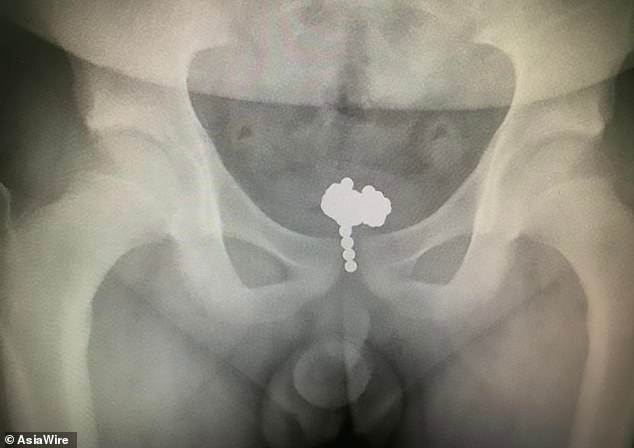

The boy from east China was rushed into surgery once the X-ray showed the truth about his condition. He had more than 70 small magnetic balls pushed inside of him.

The X-ray showed just how bad the situation was for the child. He shoved the Buckyballs through the opening in his penis all the way up and into his bladder. They were gathered there preventing him from using the bathroom without extreme pain.

But he didn’t have to tell the whole truth because the x-ray did that for him. Nevertheless, the boy’s curiosity to see how many magnetic balls he could shove into the urinary tract mesmerized doctors.